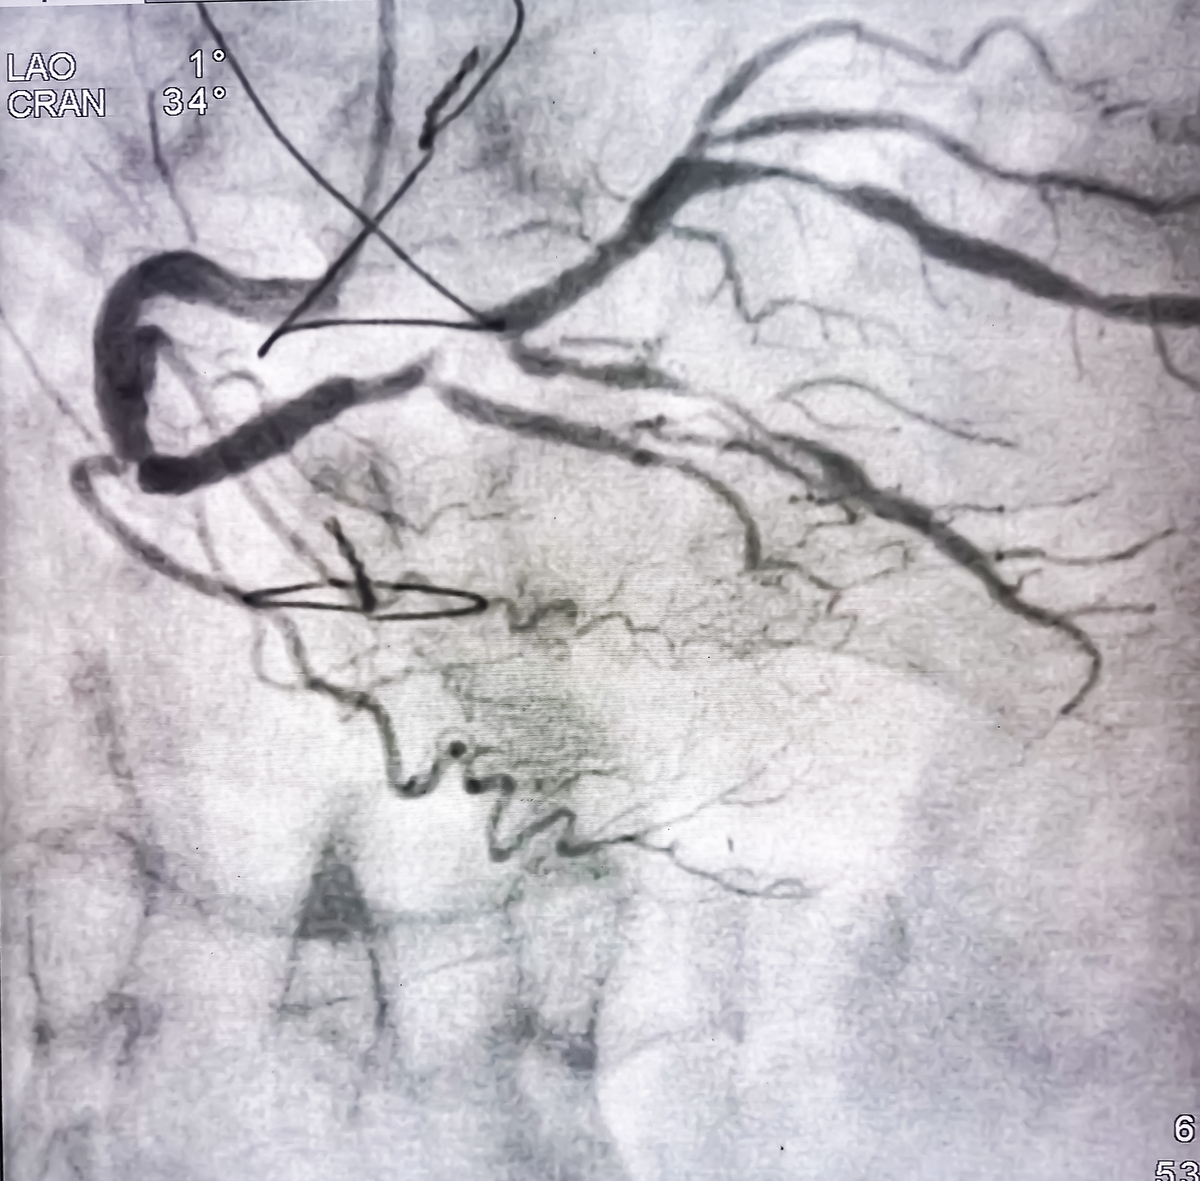

The patient in this case was initially admitted to the hospital due to neurological symptoms. During routine ultrasound examination, we observed a slightly low echogenic plaque with luminal stenosis at the origin of the right carotid artery, and a suspicious low echogenicity at the distal end of the plaque which showed slight oscillation with arterial pulsation. Additionally, color Doppler imaging showed a suspicious filling defect. Therefore, we highly suspected acute thrombus formation and performed contrast-enhanced ultrasound after obtaining the patient's informed consent. Contrast-enhanced ultrasound not only confirmed the unenhanced floating thrombus at the distal end of the plaque, but also revealed small ulcers and abundant neovascularization within the plaque that were not visible on routine ultrasound. This case of contrast-enhanced ultrasound demonstrated the entire process of vulnerable carotid plaque rupture leading to stroke.